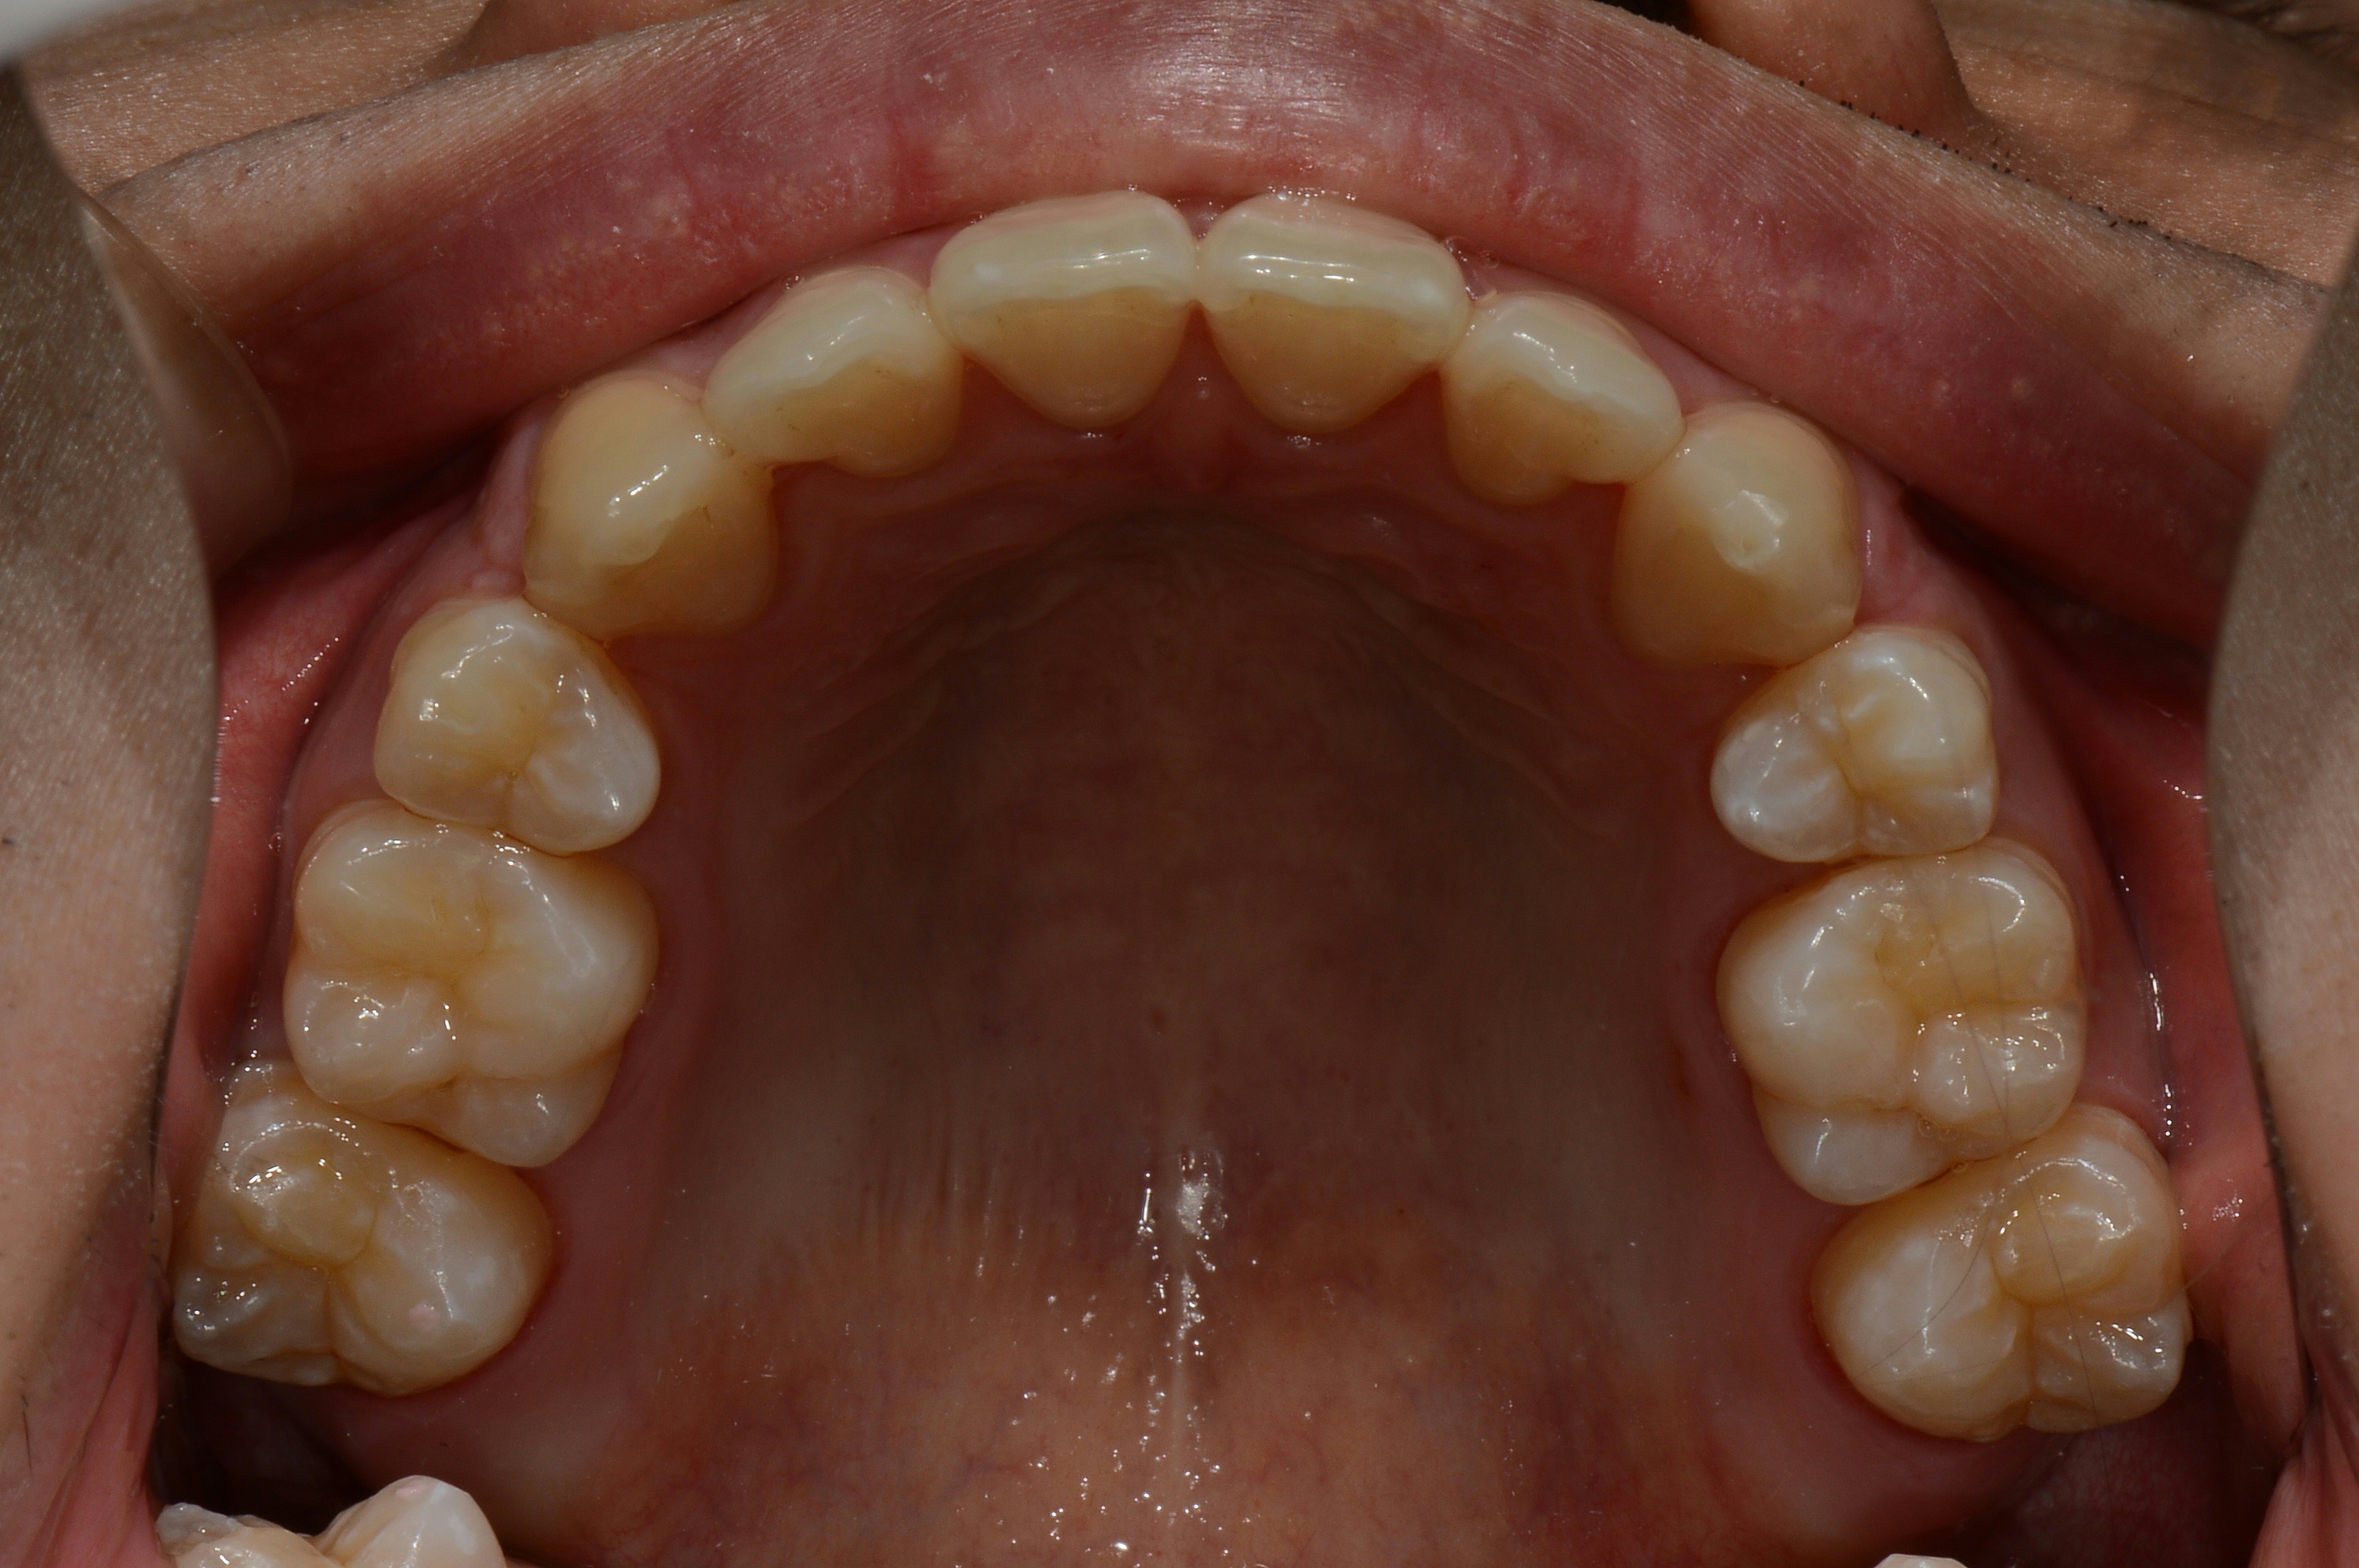

치료 후 사진입니다.